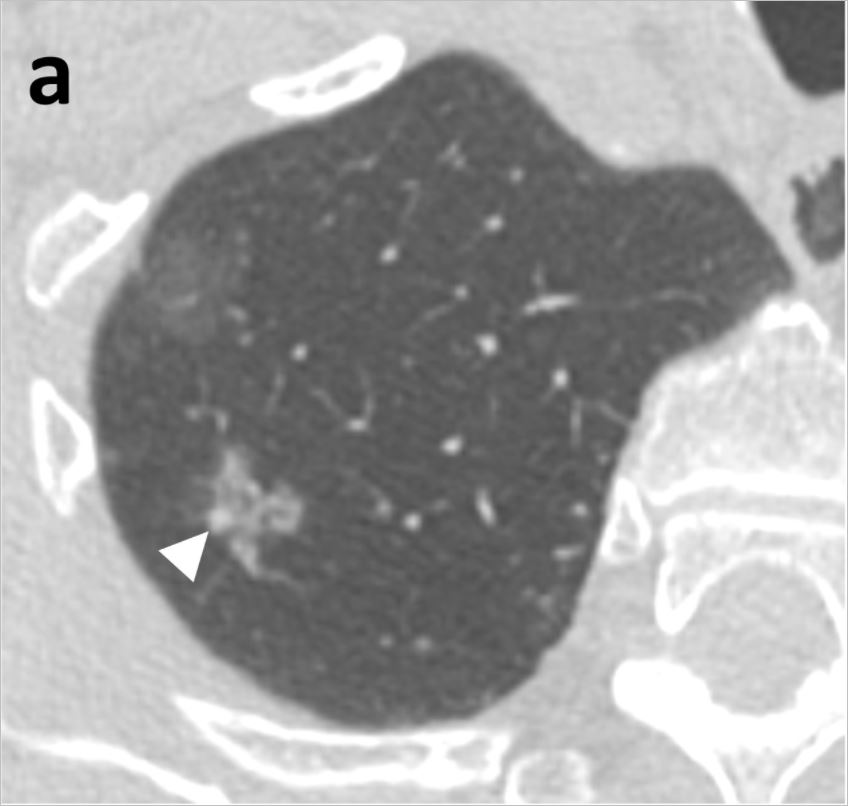

그렇다면 홍혜걸이 말한 간유리음이란 뭘까요?

간유리 음영이란 CT로 폐를 촬영할 경우 영상에 뿌옇게 유리를 갈아 뿌려 놓은 것 같은 모양을 하고 있다면 붙여진 이름입니다. 아직까지 어떻게 치료해야 할지에 대해 명확한 기준이 나와 있지 않습니다. 최근 연구 결과에 의하면 간유리 음영의 대부분이 조직검사 결과 암이었다고 합니다.

연세대 강남세브란스병원 흉부외과 이성수, 문덕환 교수 연구팀은 2012년 5월부터 2016년 12월까지 강남세브란스병원에서 폐암이 의심돼 수술받은 환자 중 순수 간유리 음영으로 진단된 36명, 44례를 분석한 결과, 침윤성 선암이 10례(22.7%), 최소침윤성 선암이 15례(34.1%), 제자리암종 18례(40.9%), 비정형샘종증식이 1례(2.3%)로 나타났다고 24일 밝혔다. 제자리암종은 암세포가 기저막을 침윤하지 않고 상피층 내에만 있어 0기암이라고도 불리는데, 제자리암종까지 포함할 경우 간유리 음영 결절의 97% 이상이 암이었다는 뜻이다. 비정형샘종증식도 폐암이 되기 직전의 병변이기 때문에 사실상 분석한 간유리음영 모두 암으로 볼 수 있다고 연구팀은 설명했다.